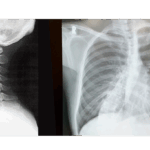

姿勢矯正には、まず、どこが悪いのか?患者様の訴えから、施術者が客観的に検査してその原因を探します。姿勢の悪い主な原因としては、猫背、円背、ストレートネック、交通事故の後遺症、手術後の後遺症、足の捻挫やぎっくり腰の庇いなど様々です。

- ストレートネック